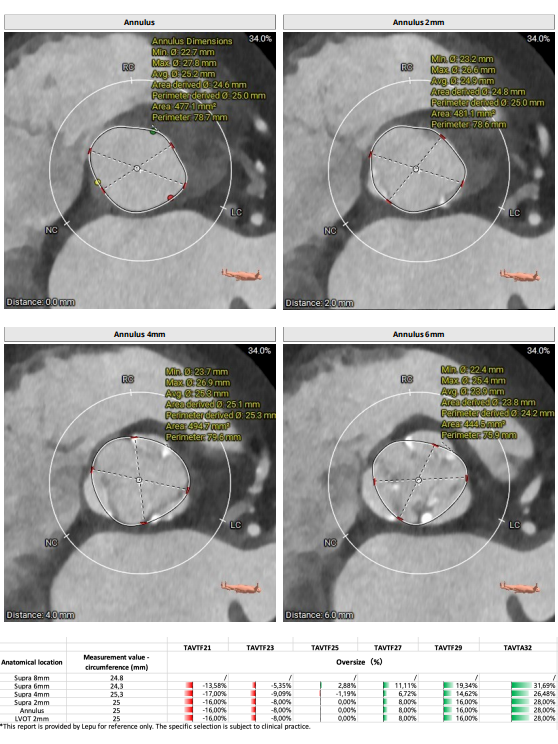

CASE2.

【术前CT】